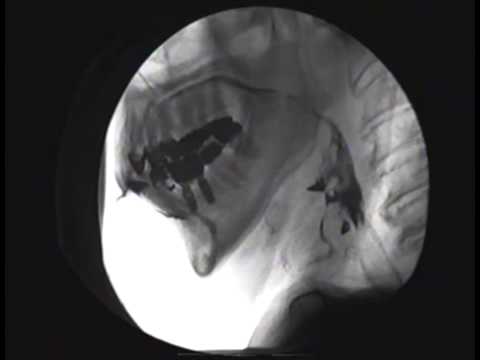

| κατάποση | 12-07-2015 | |